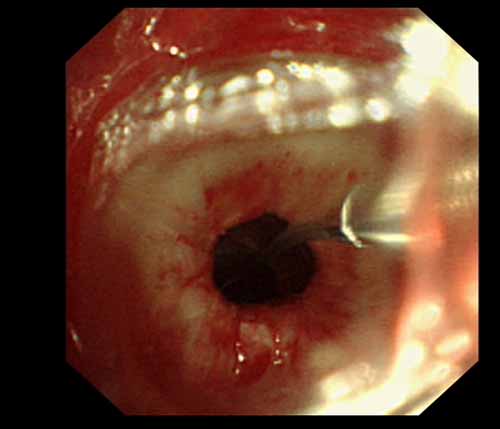

患者李某某,女,45歲,因氣管插管咳嗽、喘憋10天入院。頸部CT檢查示聲門下約20mm處氣管明顯狹窄,狹窄段長約26mm,最窄處直徑約4.4mm。支氣管鏡檢查見聲門下約2cm氣管呈漏斗狀縮窄,直徑約4-5mm,支氣管鏡無法通過。經(jīng)科室討論,決定行電子支氣管鏡下氣管球囊擴張治療。與患者及家屬充分溝通并經(jīng)三方見證談話簽署知情同意書后,在患者持續(xù)吸氧、局麻下,科主任于世倫主任醫(yī)師帶領(lǐng)治療小組為患者實行電子支氣管鏡下氣管球囊擴張術(shù)。手術(shù)過程順利,出血量很少,術(shù)后患者呼吸困難癥狀即可明顯緩解。10天后行二次擴張,患者日?;顒訜o明顯喘憋,二次術(shù)后5天出院。

術(shù)中球囊擴張